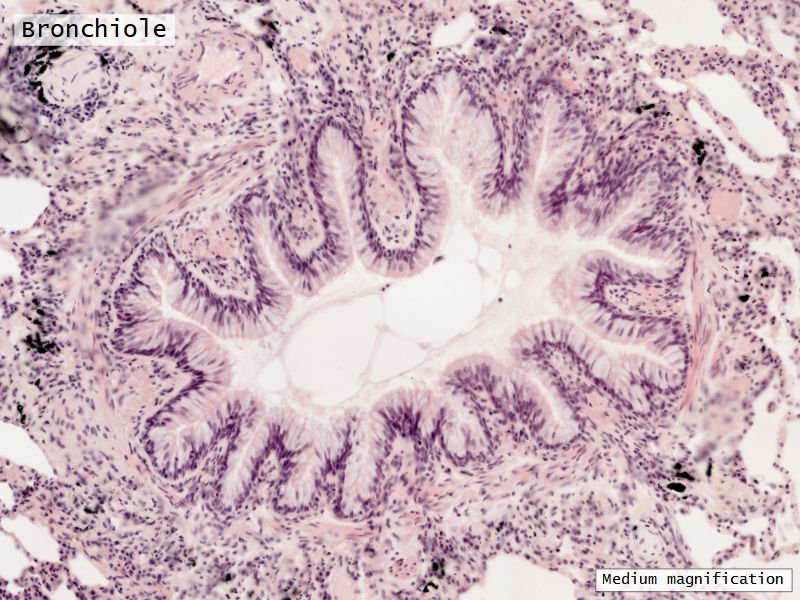

Respiratory epithelium

- Pseudostratified

- Ciliated

- Columnar

- Epithelium with

- 4 Cells

- Ciliated columnar cells

- Non-ciliated columnar cells

- Goblet cells

- Basal cells